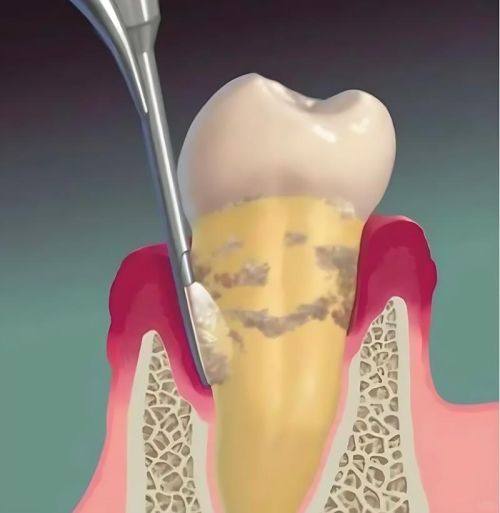

牙周治疗、牙周牙髓病治疗:能够精细诊断牙周与牙髓病变,采用规范的诊疗手段控制炎症、修复受损组织,缓解口腔疼痛不适,帮助患者修复口腔健康。

患者张先生 牙周治疗项目“我一直受慢性牙周炎困扰,牙龈经常出血红肿,杨医生仔细检查后制定了针对性的治疗方案,经过一段时间的治疗,症状明显好转,医生态度也特别耐心,会解答我所有的疑问。”